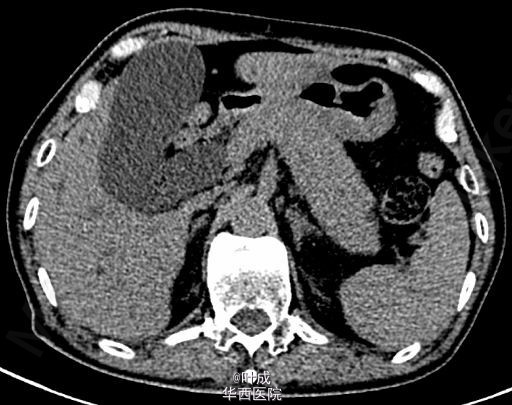

患者男,75岁,因“反复右上腹疼痛3+年,加重10天”入院,急诊查血清淀粉酶 530 IU/L,脂肪酶 466 IU/L,总胆红素 151.6 umol/L,直接胆红素 136.2 umol/L;腹部CT示胰腺肿胀,肝内外胆管扩张,胆囊结石(图1-2)。予对症处理同时行ERCP,见十二指肠主乳头肿大(图3),造影示胆总管增粗,胆道未发现结石。